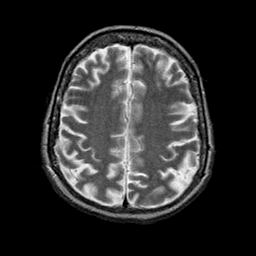

Alzheimer's disease: overlay -- Slice #18

[Home][Help][Clinical] Slice 18